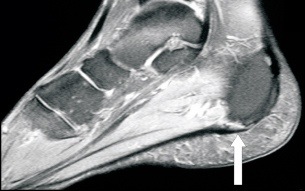

Stress fractures will often present with constant pain that lingers most of the day and doesn’t improve with running or activity. It actually will get worse. Stress fracture pain is also very point tender, meaning the pain is in an isolated area and very sharp when pressing in that area. Stress fractures are most common to the fourth metatarsal in the foot, the tibia of the lower leg, and vary rarely in the heel bone (calcaneal stress fracture). Plantar fasciitis is commonly misdiagnosed as a stress fracture too often after a bone scan is ordered for further examination. MRI is the study of choice to diagnose a stress fracture when it is being considered in any runner. Many times an xray will not show signs of a stress fracture for 2 weeks when and MRI can show immediate changes. This is crucial because altering training patterns for two weeks when waiting for xray changes can be detrimental for any runner.